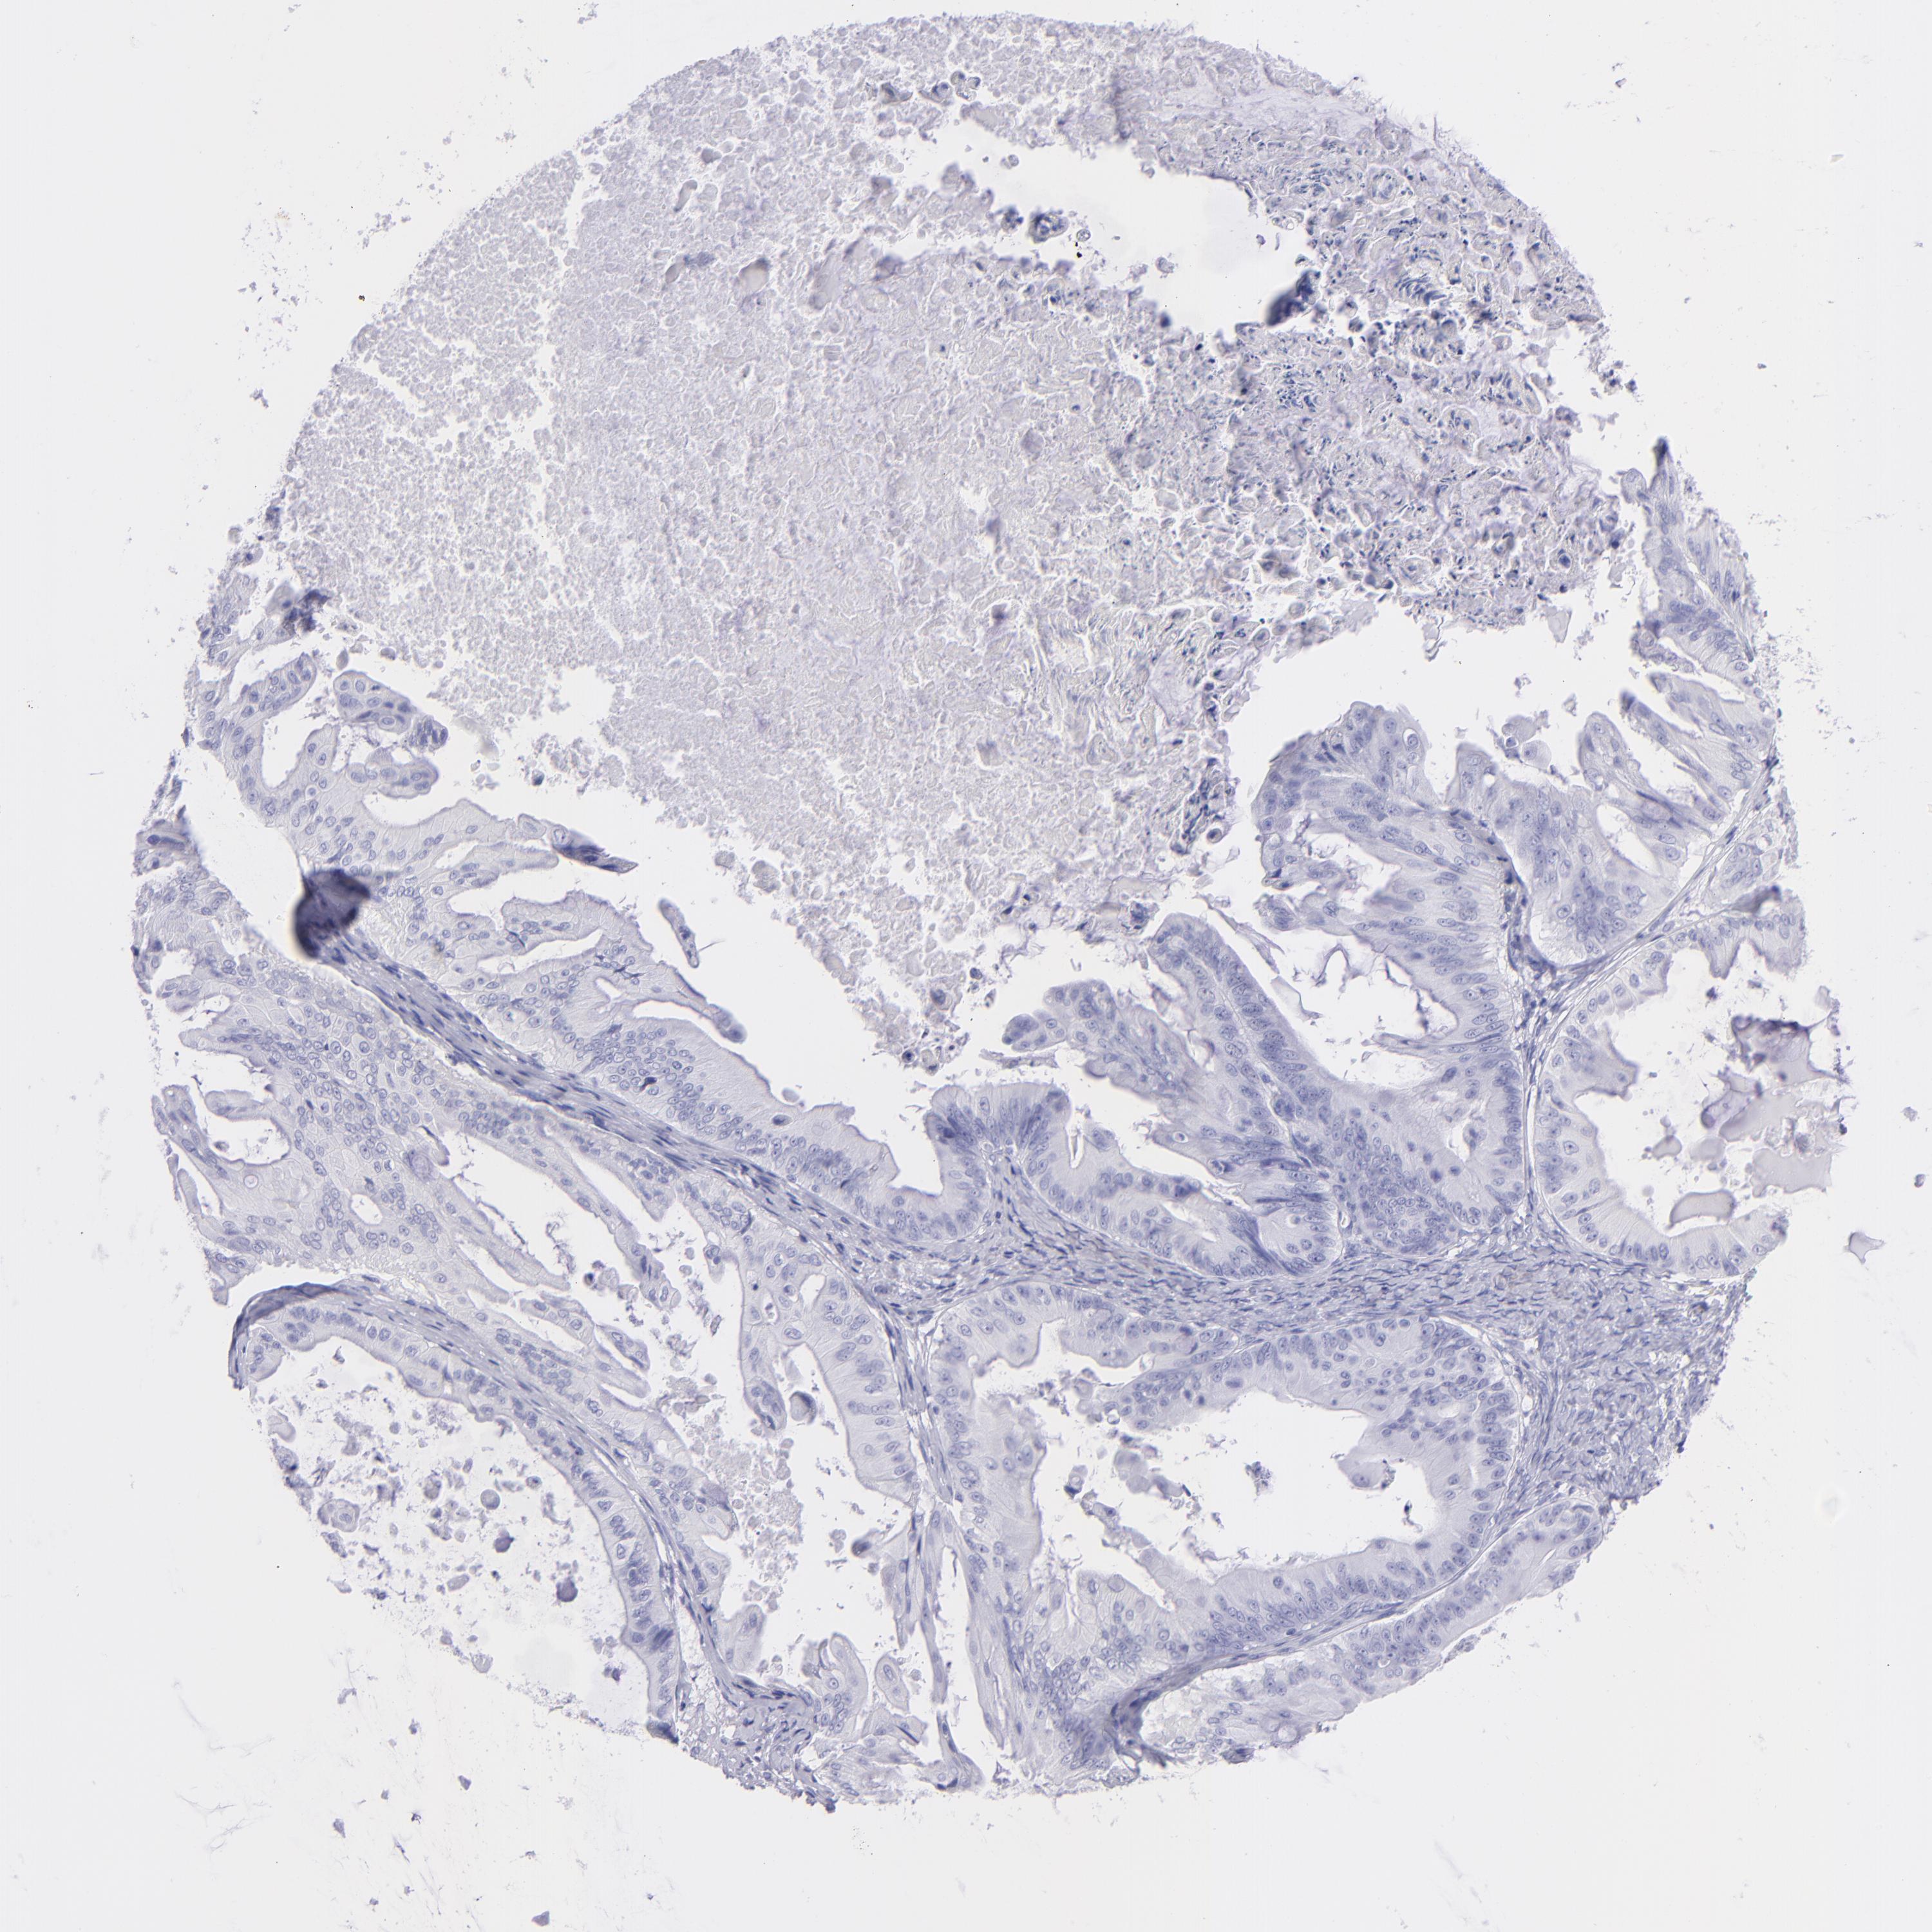

OVARIAN CANCER - Protein expressioni

A mouse-over function shows sample information and annotation data. Click on an image to view it in a full screen mode. Samples can be filtered based on level of antibody staining by selecting one or several of the following categories: high, medium, low and not detected. The assay and annotation is described here.

Note that samples used for immunohistochemistry by the Human Protein Atlas do not correspond to samples in the TCGA dataset.

Antibody stainingi

Antibody staining in the annotated cell types in the current human tissue is reported as not detected, low, medium, or high, based on conventional immunohistochemistry profiling in selected tissues. This score is based on the combination of the staining intensity and fraction of stained cells.

Each image is clickable and will lead to virtual microscopy that enables deeper exploration of all samples and also displays staining intensity scores, fraction scores and subcellular localization as well as patient and tissue information for each sample.

HPA023266

HPA023278

HPA023280

HPA023338

CAB002672

Cystadenocarcinoma, serous, NOS

Carcinoma, endometroid

Cystadenocarcinoma, mucinous, NOS

Carcinoma, NOS